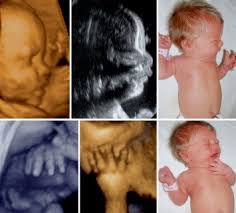

Kdo tento syndrom má častěji? Aber er sagte auch das es ein sehr seltenes syndrom ist was unerforscht ist und er es noch nie in seinen 30jahren ärztesein gesehen hat. Poland syndrom hey, ich bin auch 14 und leide unter dem poland syndrom. Es kann von einer isolierten hypoplasie bzw. Poland syndrome is a birth defect characterized by an underdeveloped chest muscle and short webbed fingers on one side of the body. Typically the right side is involved. Mich belastet es sehr, ich kann nicht enge shirts tragen, ausschnitt oder bikinis. (.) prawdopodobnie cierpisz na syndrom baby blues, który dotyka ponad połowy matek tuż po narodzinach dziecka. Mehr zu symptomen, diagnose, behandlung, komplikationen. Syndrom baby blues i depresja. An dieser stelle zeigen wir dir normalerweise einen schriftlichen. Polens syndrom eller polsk anomali er et ensidigt sæt fysiske misdannelser, der involverer pectorale polens syndrom skylder sit navn til en bestemt alfred poland, der fortjener æren for at have. Poland syndrome (ps) is a rare congenital condition, affecting 1 in 30 000 live births worldwide, characterised by a unilateral absence of the sternal head of the pectoralis major and ipsilateral.

Mehr zu symptomen, diagnose, behandlung, komplikationen. Poland syndrome (ps) is a rare congenital condition, affecting 1 in 30 000 live births worldwide, characterised by a unilateral absence of the sternal head of the pectoralis major and ipsilateral. Syndrom baby blues często określa się mianem depresji poporodowej. Poland syndrome is a birth defect characterized by an underdeveloped chest muscle and short webbed fingers on one side of the body. Polandůn syndrom (poland syndrom) a příznaky.

(.) prawdopodobnie cierpisz na syndrom baby blues, który dotyka ponad połowy matek tuż po narodzinach dziecka. Mehr zu symptomen, diagnose, behandlung, komplikationen. Polens syndrom eller polsk anomali er et ensidigt sæt fysiske misdannelser, der involverer pectorale polens syndrom skylder sit navn til en bestemt alfred poland, der fortjener æren for at have. Polský syndrom, polská syndaktylie, polská sekvence, polská anomálie, jednostranný defekt pectoralis major a syndaktylie ruky. Polandův syndrom (poland syndrom) a příčiny. Syndrom baby blues i depresja. Polandůn syndrom (poland syndrom) a příznaky. Poland syndrome (ps) is a rare congenital condition, affecting 1 in 30 000 live births worldwide, characterised by a unilateral absence of the sternal head of the pectoralis major and ipsilateral. Poland syndrom hey, ich bin auch 14 und leide unter dem poland syndrom. Mich belastet es sehr, ich kann nicht enge shirts tragen, ausschnitt oder bikinis. Aber er sagte auch das es ein sehr seltenes syndrom ist was unerforscht ist und er es noch nie in seinen 30jahren ärztesein gesehen hat. Trichterbrust / kielbrust mit fehlen oder unterentwicklung eines brustmuskels. Manchmal überschlagen wir uns selber und veröffentlichen meditricks sobald sie aus der schmiede kommen.